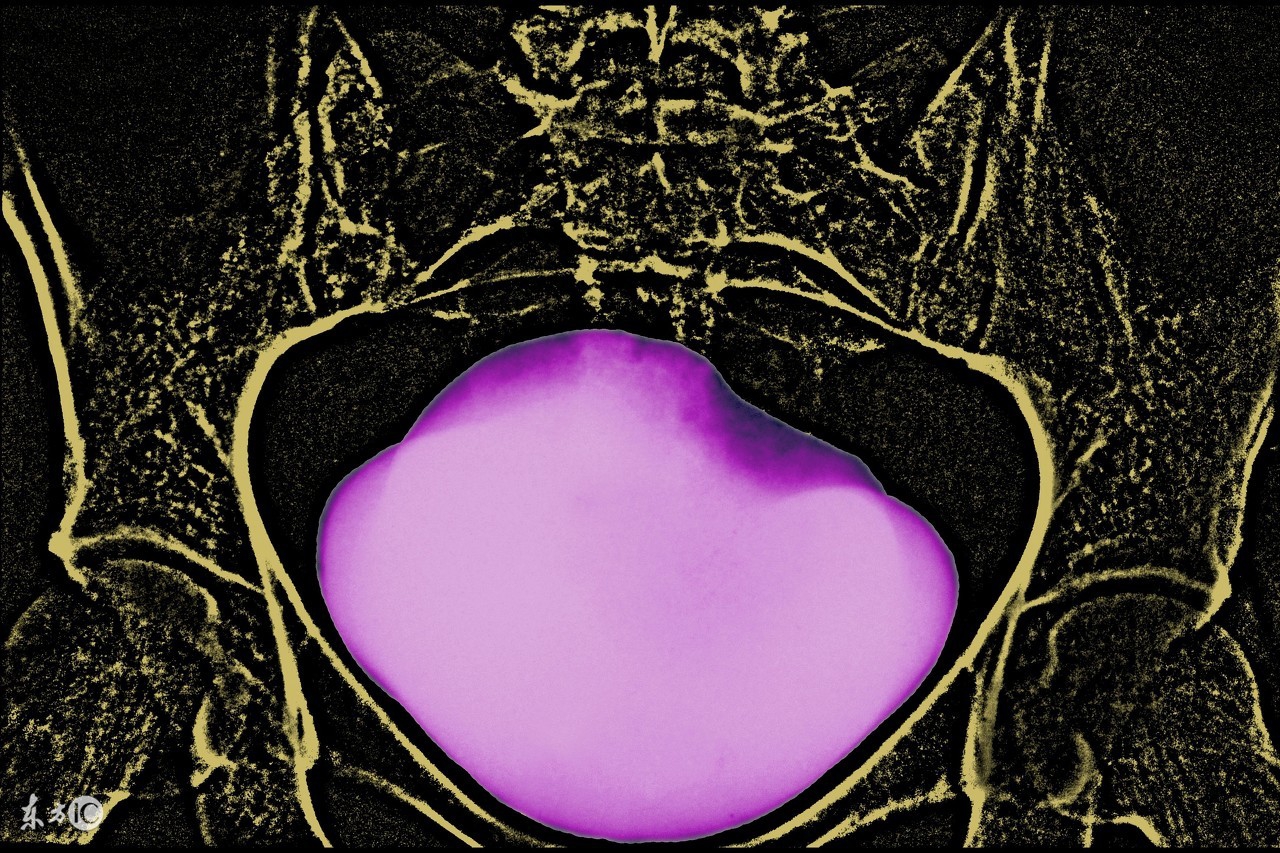

腹膜内型膀胱破裂是膀胱严重损伤的一种常见类型, 多在膀胱充盈时发生。

病因 膀胱属腹膜间位器官, 膀胱空虚时深藏骨盆内, 四周有骨盆保护, 一般不易受伤。腹膜外型膀胱破裂常由于外力伤及膀胱前下壁所致, 当膀胱充盈变薄时高出耻骨联合上的膀胱顶部及后壁受到*力暴**伤可导致腹膜内型膀胱破裂。所受*力暴**伤如车祸、撞击伤、挤压伤, 部分伴骨盆骨折;医源性损伤见于内腔镜操作、盆腔手术误伤等, 自发性破裂多见于醉酒后膀胱破裂、病变膀胱(如膀胱结核或肿瘤)过度充盈、前列腺肥大、尿潴留过度引起。

诊断 B 超检查为膀胱破裂首选、简捷的检查手段 , 典型者有膀胱空虚或不充盈, 膀胱壁连续性中断、裂口处血块形成、肠间隙或膀胱周边积液等表现。导尿及膀胱灌注试验是快速、简单、有效的诊断方法, 结合腹腔穿刺可进一步提高确诊率 。但如果膀胱裂口位于顶部、裂口小、裂口血凝块或肠管阻塞、注水量少时存在假阴性。经导尿管注水同时下腹B 超扫查有助早期明确诊断。膀胱造影腹部平片或张力性膀胱造影法可见造影剂通过裂口进入腹腔而确诊。分析临床上误诊或漏诊与以下因素有关: